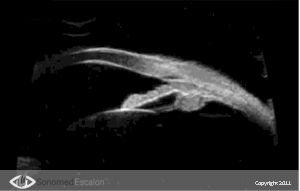

?сследование при помощи VuMAX® функций проходимости в случаях трабекулэктомии и конъюнктивальном химозе, можно оценить успешность и эффективность проведенных пост-оперативных вмешательств таких, как фильтрующая хирургия. Кроме того, VuMAX® обеспечивает четкую визуализацию Шлеммова канала, что необходимо в случаях проведения вискоканалостомии.